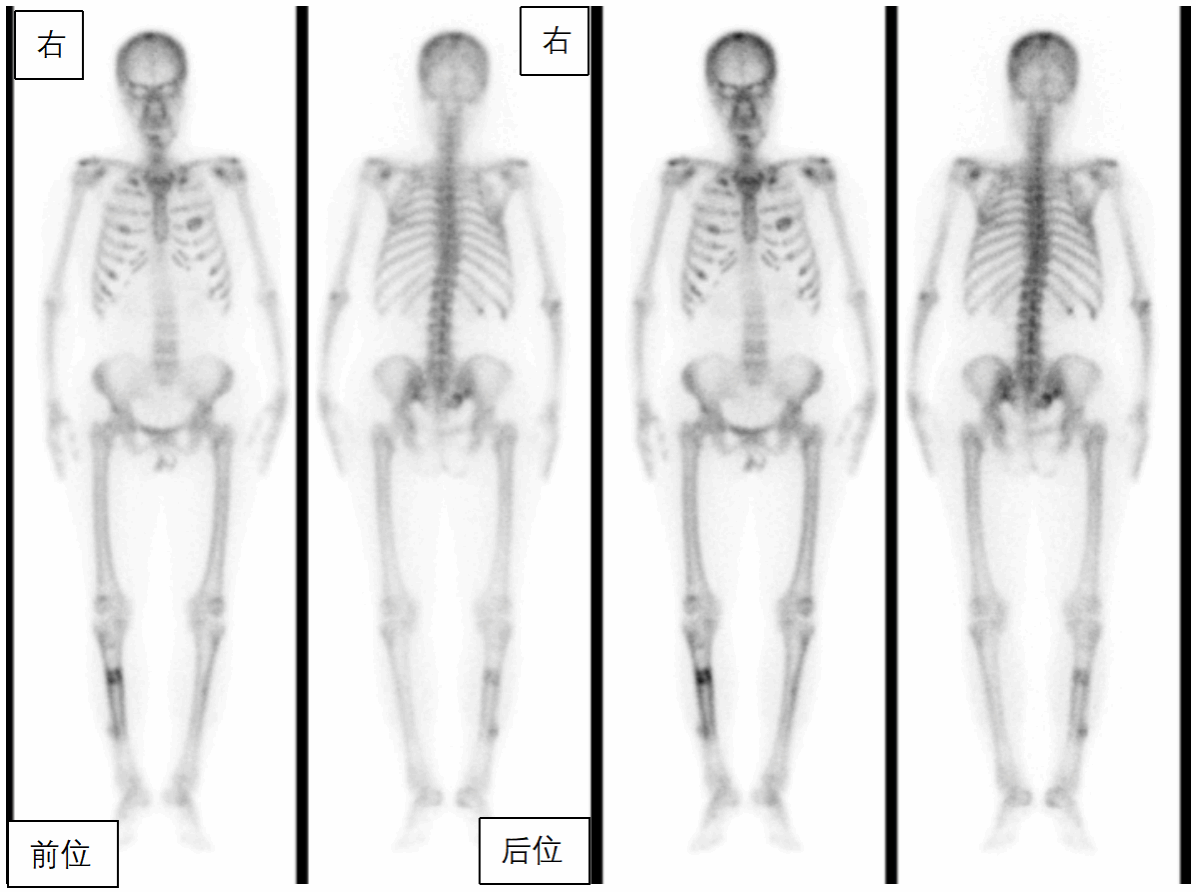

段阿姨,59岁,因腰背部疼痛1月,外院查CT示肋骨、骶骨骨质异常,骨转移?遂来核医学科行全身骨显像,判断是否是骨转移,图像(图1)如下:

全身骨骼显像剂分布弥漫性增强,肩胛骨、双侧部分肋骨、骶骨、右胫骨存在灶性显像剂异常浓聚,双肾及软组织本底显示不清,呈“超级骨显像”。